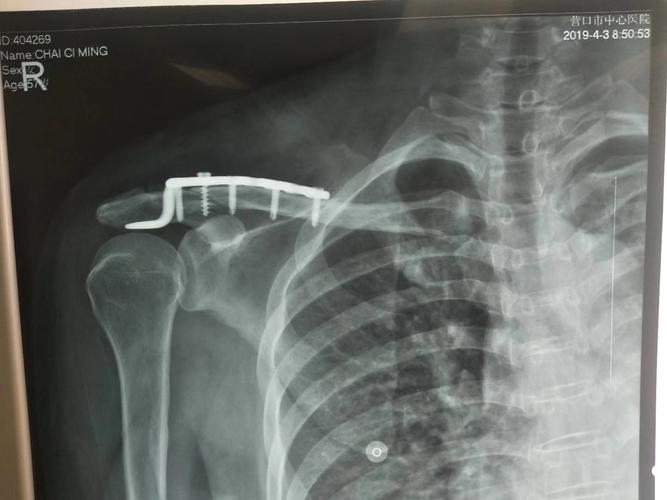

锁骨骨折有鼓包图片

锁骨骨折有鼓包图片,锁骨错位重叠长好图片

呼市妇幼保健院综合外科完成首例弹性髓内针治疗锁骨骨折患儿

锁骨骨折手术图片

锁骨骨折钢板图片